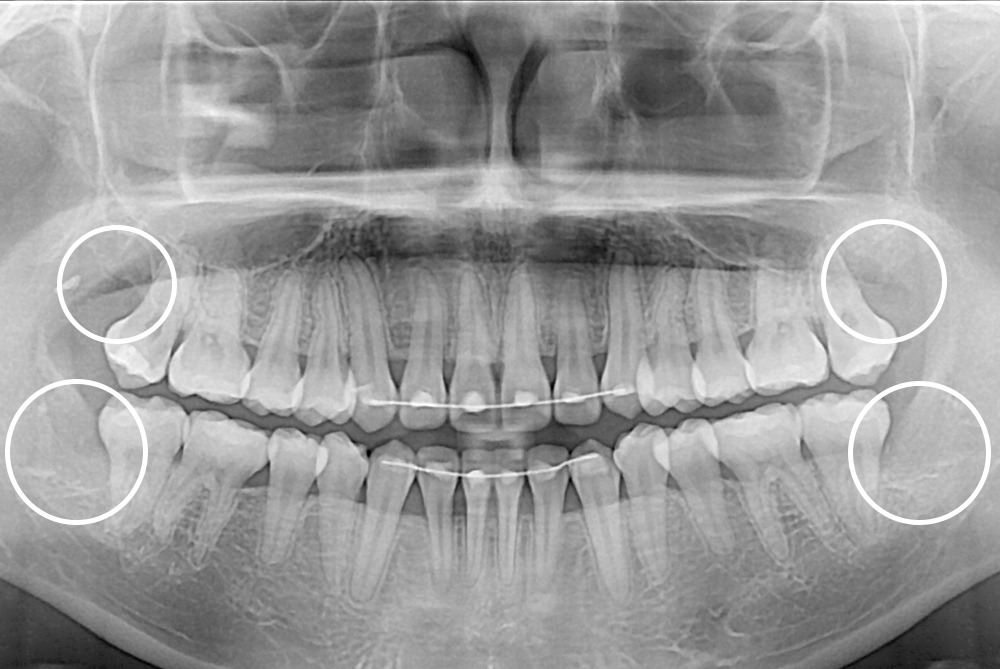

[사랑니] 매복 사랑니 발치

치료후 : 2018-03-13

세종치과는 구강악안면외과학 박사이신 원장님이 발치하는 치과입니다.